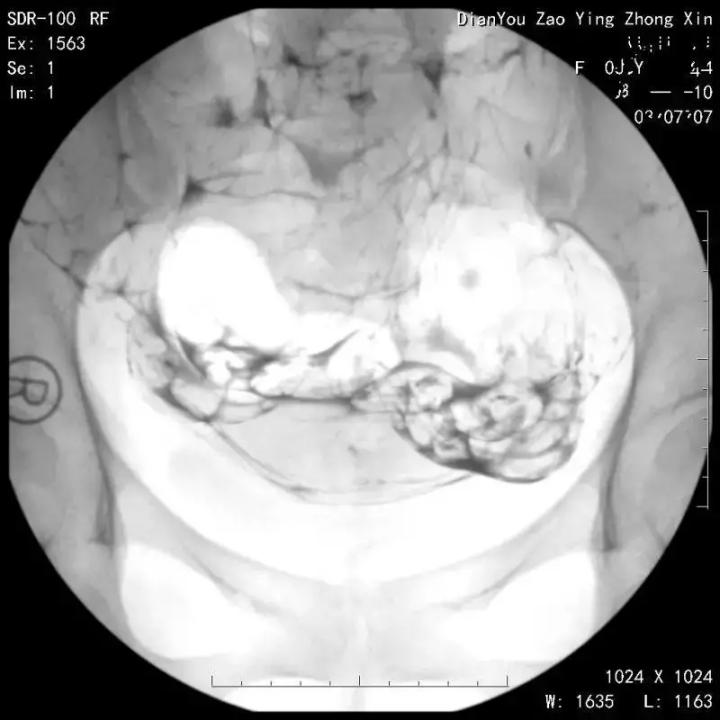

目前,临床上做输卵管造影术主要采用碘油和碘水两种造影材料。但是,碘油和碘水哪个更好,该如何选择,很多患者并不清楚。

碘油粘稠度高,张力大,一定程度上可以使输卵管黏膜轻度粘连时被分离扩张,另外碘油还有一定的局部消炎的作用, 所以碘化油对输卵管及远端周围组织炎症有一定的治疗作用,术后的自然怀孕率也高于碘水造影。

碘水为水溶性,粘稠度低,流速快、弥散快,当日便能报告检查结果,方便快捷。

但是碘水推注后即刻显影,子宫输卵管边缘部分显影欠佳,细微病变不易观察,会导致盆腔弥散过快,而遗漏对侧输卵管阻塞的诊断。再加上其流速快,工作人员往往不易捕捉到输卵管图像,减少了准确度。

碘油在人体残留时间较长,刺激大,容易造成肉芽肿;而碘水无明显毒副作用、无损伤,注入10-30分钟即被吸收,后经肾脏通过尿液排出。

与碘油造影剂相比,碘水造影剂因为检查时间短、无毒副作用、损伤小、精准度高、而且出报告快的优势,受到广大患者的一致认可。综上所述,子宫输卵管碘油造影诊断更准确、更客观,更有利于临床上的诊断和治疗,而子宫输卵管碘水造影并发症相对较少,安全性更好。